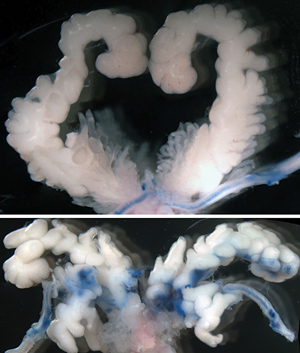

Figure 1: In male mice with the β-cateninC429S mutation, the sperm pathway (blue) is bifurcated (bottom). The same pathway in a healthy mouse is shown at the top.Reproduced from Ref. 1 and licensed under CC BY 4.0 © 2014 T. Murata et al.

Closer inspection of mice of this strain, called β-cateninC429S, revealed that the male testes and female ovaries were normal. Other parts of the sexual anatomy, however, harbored specific and unusual malformations. In the males, the seminal vesicles were abnormally duplicated, resulting in detoured sperm transportation routes (Fig. 1). In the females, the normal opening of the vagina was absent—a major obstacle to natural conception. These malformations prevented successful conception from occurring despite normal egg and sperm production.